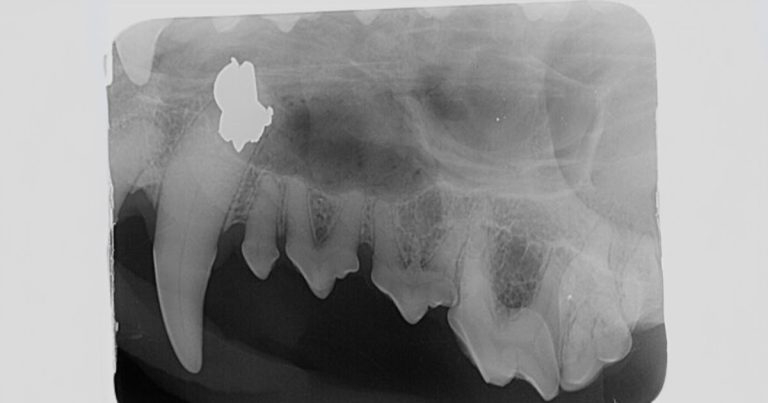

A vet team found an airgun pellet in the nasal passage of a dog rehomed from Bosnia when it was radiographed as part of a dental assessment.

X-rays picked up pellets in the thorax and left antebrachium, and a healed fracture in the left ulna dates the shooting to the dog’s time in Bosnia.

“The patient was booked for routine dentistry, which at our clinic is called a comprehensive oral assessment, including full mouth radiographs. There was in fact need to extract teeth, due to periodontitis and tooth resorption, but the story of interest was the accidental discovery of the airgun pellet in the nasal cavity.